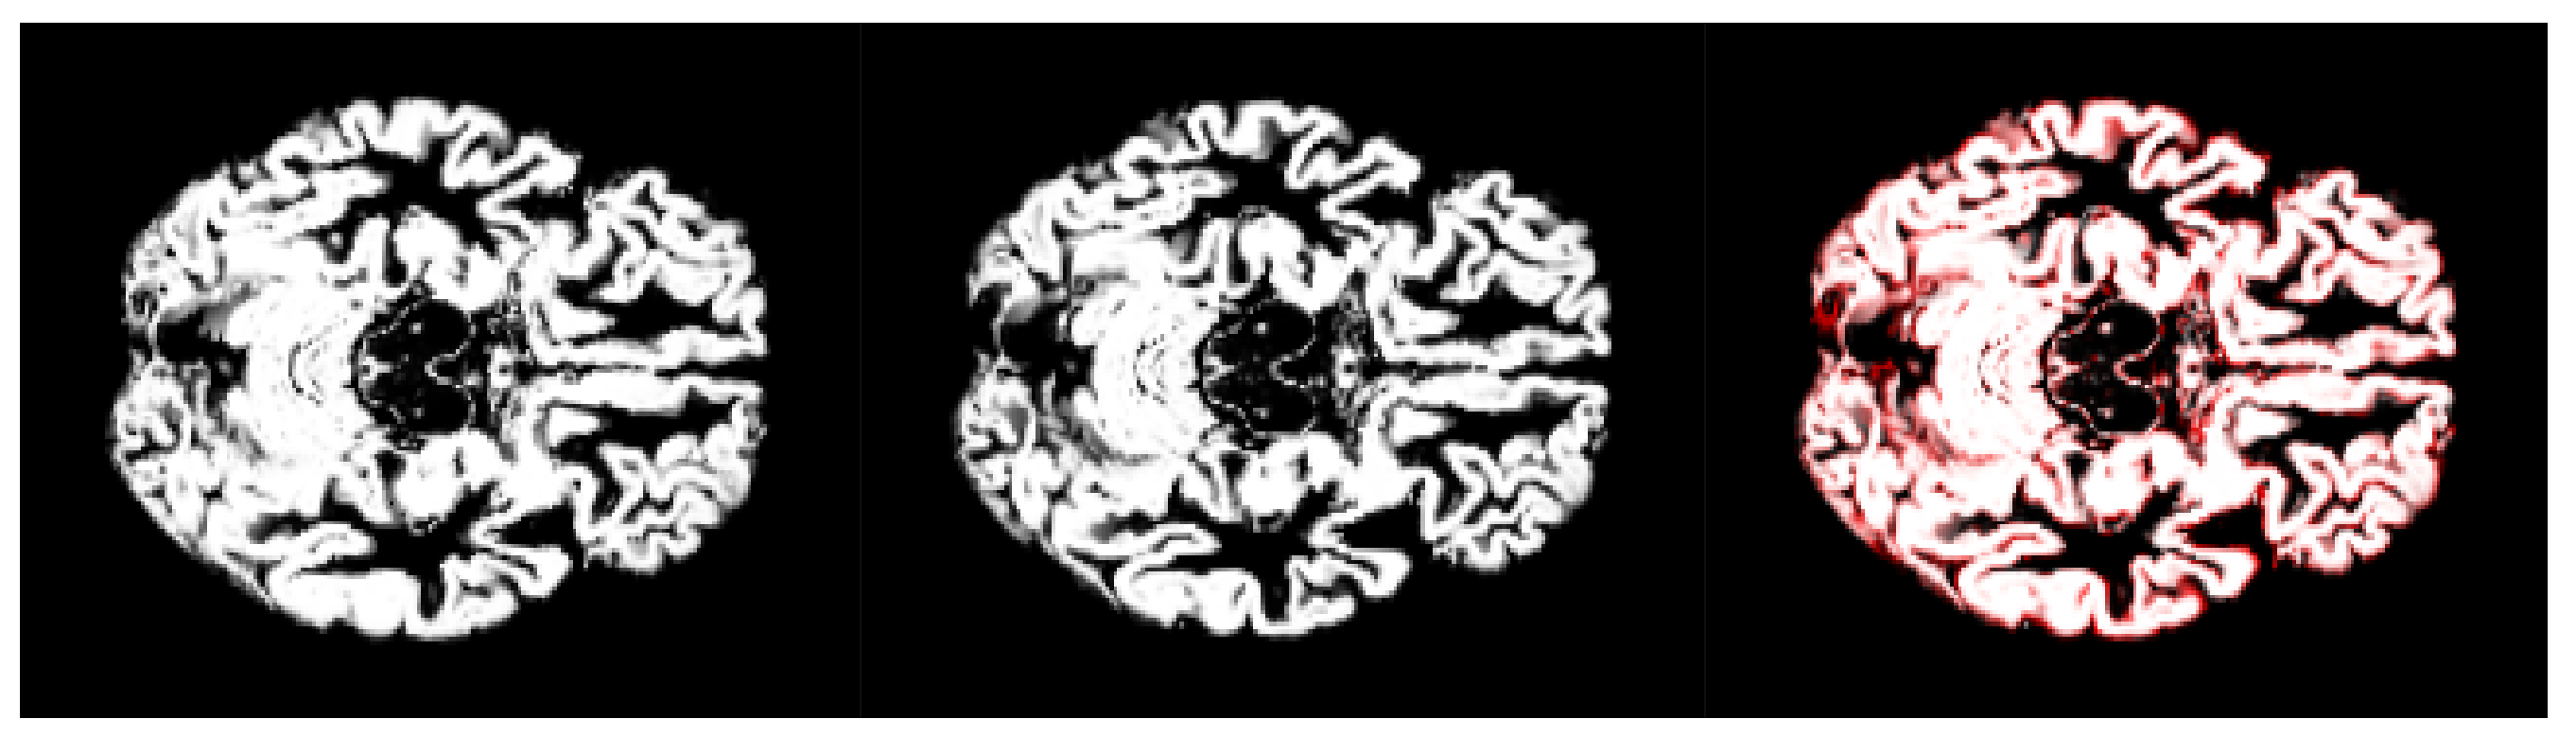

- We have introduced the notion of significant pixels, i.e., the pixels of the MRI images where the white (resp. gray) matter decays in the considered two-year time span, significantly differ between and subjects. The number of significant pixels, in the brain slices where the phenomenon mostly appeared, according to the different values obtained after performing a permutation test on all the pixels of the images, i.e., , , and , was about 4%, 2%, and 1.5% of the totality of the white matter and slightly more, i.e., 6%, 4%, and 2.5%, of the totality of the gray matter. Such a small number of significant pixels is sufficient to discriminate between and , as reported in Table 2 and Table 3, using the K-means clustering technique. Not surprisingly, when considering the white matter, all the and subjects were correctly clustered, i.e., the white matter decay of subjects significantly differed from that of ones. On the other hand, when considering gray matter, the subjects were correctly classified, while 6 of the 40 subjects were assigned to the class, with a percentage of error of 15%. This can be ascribed to the fact that Alzheimer’s disease strongly impacts on the white matter first, and later leads to the decay of the gray matter.We also underline that, according to the wide and consolidated literature, the most involved areas of the brain affected by Alzheimer’s decay are the medial portion of the temporal lobe, where the hippocampus, amygdala, entoryl cortex, and parahippocampal cortex reside. These areas are located inside the selected slice intervals where most of the significant pixels were detected. As an example, Figure 7 shows the significant pixels of slice 58, where a peak in the white and gray matter occurred, with the involved brain areas highlighted.